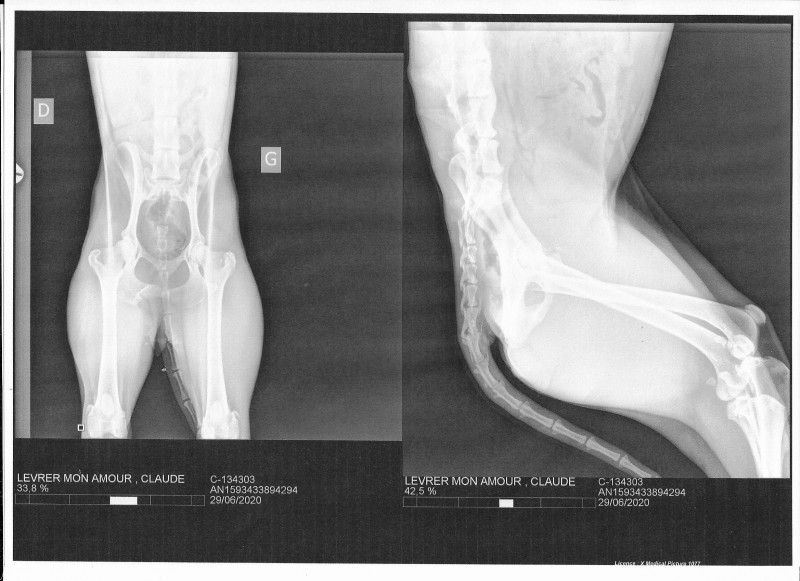

Claudya a vu un ostéopathe et nous avons consulté un spécialiste qui a fait des radios.

.jpg)

Claude (Claudya) a été retrouvée par des bénévoles espagnoles sans force avec de nombreuses blessures et dans un état de dénutrition avancé. Les vétérinaires espagnols pensaient qu’elle avait soit un cal osseux, une arthrose du dos ou une ancienne lésion. Il afallu du temps pour qu’elle récupère et elle vivait normalement.